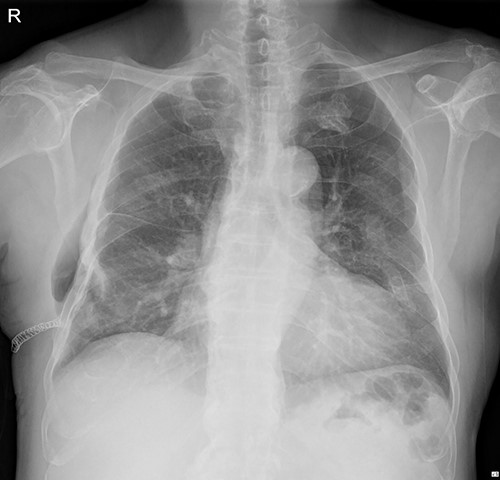

On 25 November 2021, a 68-year-old male, a victim of a motor vehicle accident, presented with multiple rib fractures and hemopneumothorax in the right hemithorax. On hospital Day 2, oxygen saturation gradually dropped under 90% despite proper support, and the patient’s right chest wall showed a newly occurred flail motion. We decided to stabilize rib fractures emergently. The operation was performed routinely, with bicortical screw fixation after exploration of the thoracic cavity. There were no specific intraoperative or postoperative events, and the patient was safely discharged from the hospital with stitches removed on hospital Day 17 (Fig. 1.).

Immediate postoperative chest X-ray after plates removal (24 February 2022).